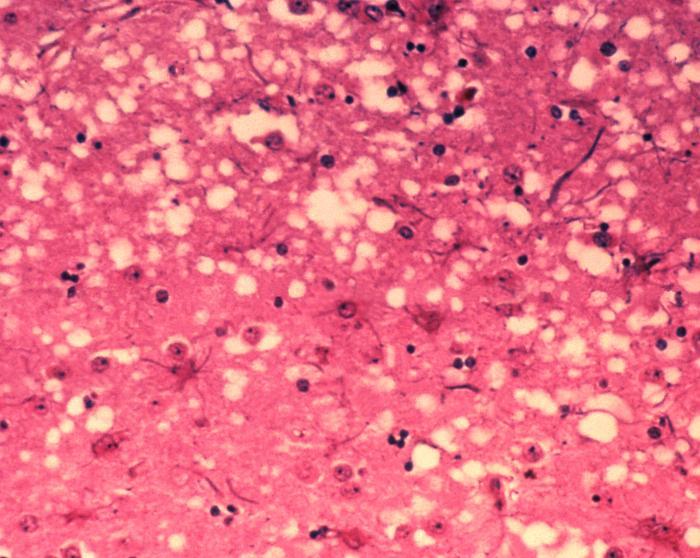

Caption: Prion fibres

Image Credit: AJC1 via flickr